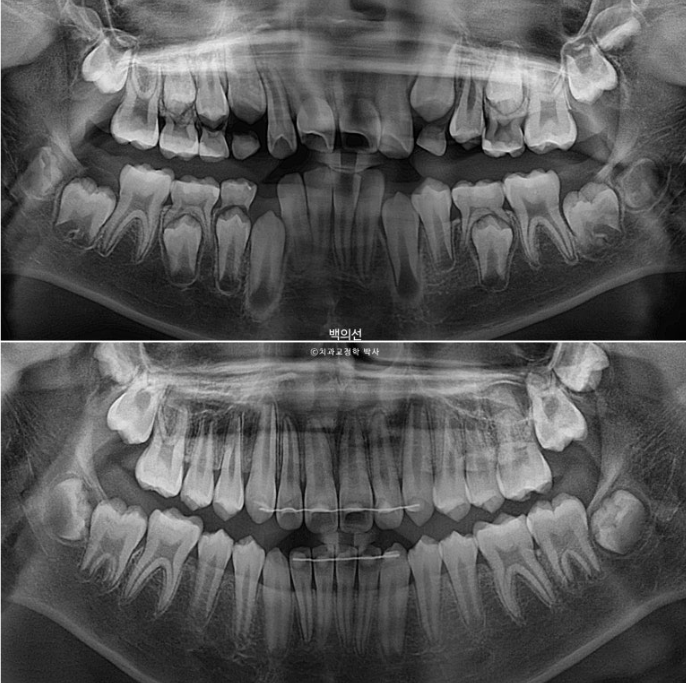

2년간의 변화를 엑스레이로 비교하면 이렇습니다.

치근흡수는 없고 치근평행도는 좋습니다.